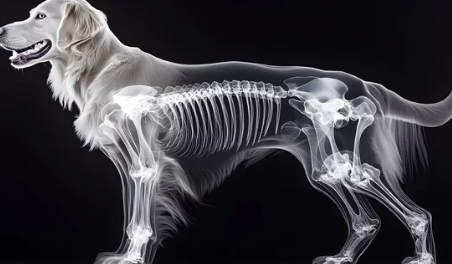

1. 강아지 관절염이란? – 알아야 대처할 수 있어요

강아지 관절염은 관절에 염증이 생겨 통증과 움직임 제한을 유발하는 질환입니다. 특히 나이가 들수록 발병 가능성이 높아지며, 소형견보다는 대형견에게 더 흔히 발생합니다.